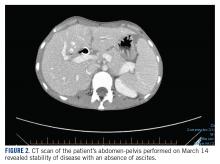

The patient’s clinical status subsequently improved, with significant reduction in her chronic abdominal pain and very minimal side effects. Clinically, the patient’s acute kidney injury resolved (from a creatinine of 272 μmol/L at discharge to 85 μmol/L after a week of treatment) and her liver enzymes normalized (from an alkaline phosphatase of 301 U/L to 83 U/L, and alanine transaminase of 111 U/L to 38 U/L). CT scan of her chest and abdomen, which was performed 1 month post treatment, revealed stability of disease with absence of ascites ( FIGURE 2 ). The patient continued to have a good response to treatment for 6 months, with no recurrence of pain or ascites.